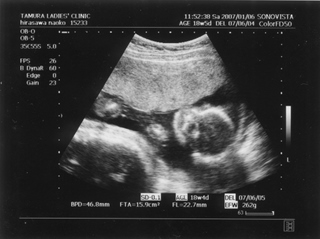

5ヶ月(18週と5日) 体重:262g BPD(頭を上から見た耳から耳の幅のような感じ):46.8㎜ FTA(お腹の断面):15.9平方㎝ FL(大腿骨長 太ももの骨の長さ):22.7㎜ 6ヶ月(22週と5日) 体重:602g BPD(児頭大横径 頭を上から見た耳から耳の幅のような感じ):57.6㎜ FTA(体幹横断面 お腹の断面):26.6平方㎝ FL(大腿骨長 太ももの骨の長さ):38.1㎜ まだこの頃は顔と上半身が収まっていました。 検診は妊娠23週までは、4週に一度なのでドキドキとワクワクです。 ちゃんと成長してるかなあなんて考えて行って、 心音をきいたり、エコーを見て毎回安心と喜びがわいてきます(*^_^*) たった4週で、体重は3倍近くにも!かわいいなあ☆ 6ヶ月の検診日ダンナっちは仕事だったから、 エコー写真を携帯で撮って送ると、 『目ん玉でてない!?』 と返事が返ってきました。 眼球がそう見えるんだろうけど、目のとても細いダンナっちには 衝撃的だったんですね(^。^;) 胎動を初めて感じた日をわたしはわかりません・・・ メモにとるなり、日記にかくなりすることをすっかり忘れてしまって、 今となって後悔<<o(>_<)o>> ダメな母親めっ と思いつつも、わたしらしいと感じ笑っています(^_^;) 12月の末に友達に、 「腸の動きか!?って思うのはあるんだけどまだよくわかんない」 と言ったのを覚えているので、12月の終わりから1月にかけての あたりなんでしょうね。 いつの間にかポッコポッコしていました! ベイビーこんなママだけどよろしく└|∵|┐♪┌|∵|┘ 6ヶ月までは、普通にそれまで履いていたジーンズも入っていたんだけど、 6ヶ月終わるころには、急に入らなくなってビックリしました~ 食生活の変化も特になかったです。 あ、ポテトチップスあまり自分で 買わなかったのに、1週間くらいブームの時期がありました!妊娠による影響かな!? 今、ベイビーはしゃっくりをしているみたいです |